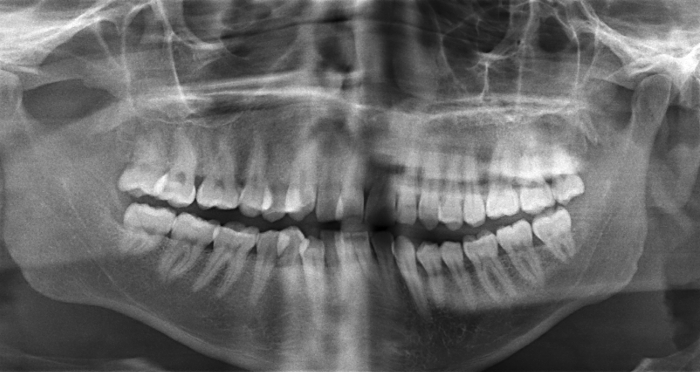

What should you be able to see with proper positioning for a panoramic?

A

• Teeth and jaws sharply depicted.

• Slight curvature of occlusal plane.

• Equal magnification on left and right side.

• No air space obstructing view of maxillary roots.

• No ghost image of cervical spine in midline